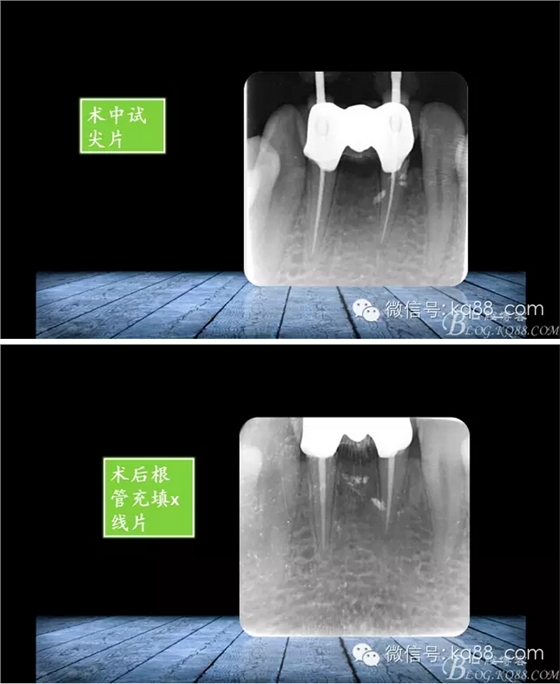

張瑞鋒:簡(jiǎn)單的事情認(rèn)真做——我的根管治療